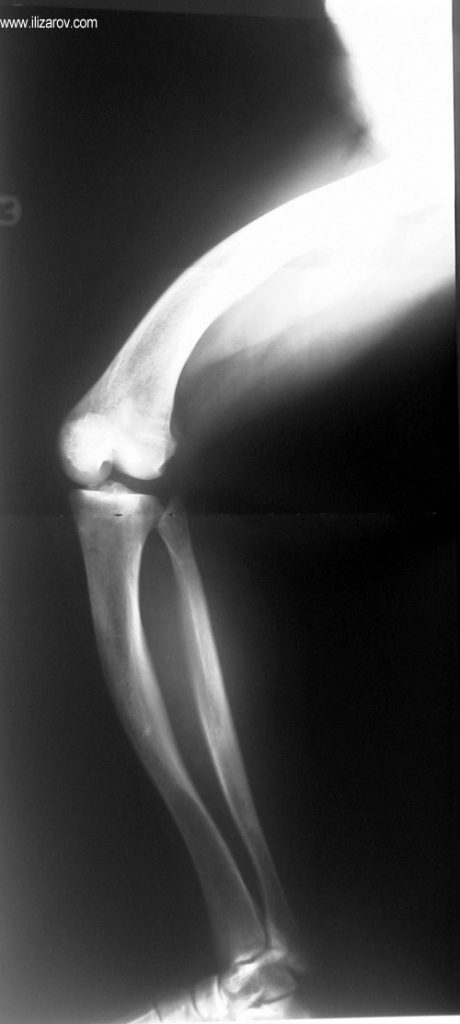

Hipofosfatemik raşitizmde anormal kemik bulguları 1 yaşından sonra belirginleşir; kısa boy ve sıklıkla diz çevresinde deformiteler (bilateral genu valgum ya da varum, tibial torsiyon, femur ve tibiada eğrilik, ‘windswept’ deformitesi) ortaya çıkar.

Hipofosfatemik raşitizmin neden olduğu bozukluk büyüme plağına çok yakın olduğu için büyük bir deformite ve ciddi dizilim bozukluğu ortaya çıkar. Bu nedenle cerrahi öncesi değerlendirmede sıklıkla birden çok deformite merkezi (CORA) bulunur ve deformitenin düzeltilmesi için birden çok seviyeden osteotomi yapılması gerekir. Deformitenin düzeltilmesi için en sık kullanılan yöntemler Ilizarov yöntemi ya da monolateral eksternal fiksatör kullanılarak akut ya da tedrici deformite düzeltilmesidir. Kliniğimizde uygulanan fiksatör yardımlı çivileme yönteminde deformite eksternal fiksatör kullanılarak akut olarak düzeltildikten sonra intramedüller çivi ile stabilizasyon sağlanmakta, uzatma yapılmayacaksa eksternal fiksatör cerrahi sona ermeden çıkartılmakta, uzatma yapılacaksa (çivi üzerinden uzatma) uzatma tamamlandıktan sonra fiksatör çıkartılmaktadır. Bu sayede tel dibi enfeksiyonu riski ortadan kalkmakta, hipofosfatemik raşitizm tedavisinde önemli sorunlar olan koreksiyon kaybı ve deformite nüksü önlenmekte, hastaya erken hareket verilerek tam yükle yürümesine izin verilmekte ve eksternal fiksatör süresi azaldığı için hasta konforu artmaktadır.